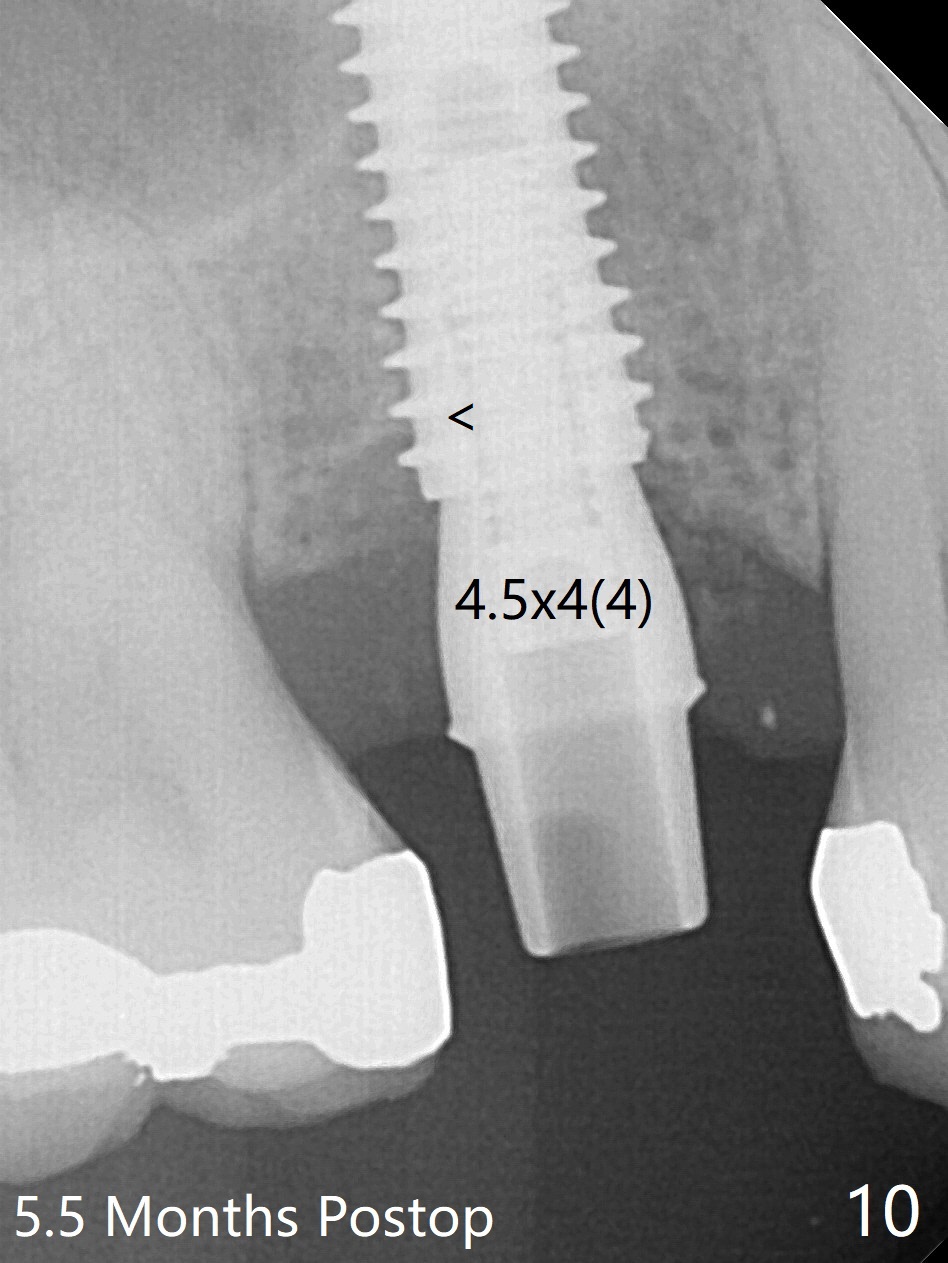

The 48-year-old man agrees to extract the tooth #4 with buccal and palatal fistulae (Fig.1,2 >) and large PARL (Fig.3 *) because of purulent discharge. The large post (Fig.3 P) is most likely associated with a longitudinal fracture. The latter is not noted until postop (Fig.4 <). Intraop finding is large amount of granulation tissue removed from the mesial apical region (Fig.3,5 *). With 10.5 mm offset, Sinus Approach Drill (19 mm) is estimated too short for sinus lift after 3x8.5 mm drill. Without careful repeated check, 2.2x10 and 2.2x11.5 mm drills are used. The sinus floor is perforated, but the membrane seems to be intact. The perforation is too small to insert PRF, but alright for allograft. Then nose blowing test shows that the sinus membrane is perforated, which seems to be repaired after placement of 2 pieces of PRF membrane, followed by another round of allograft (Fig.5 G), which is lifted by a 4x10 mm IS dummy implant. Before placement of a 4.5x11.5 mm final UF implant, allograft is placed in the 3 defective bony areas mentioned above, including the apical mesial one (Fig.6 *). But the final UF implant seems too short with non-satisfactory torque. The latter appears to be solved with the increased length of the implant (Fig.7). The gingiva around the provisional (P) is healthy without fistulae buccal (Fig.8) or palatal 17 days postop (Fig.9). A new abutment with 1 mm longer cuff is seated completely 5.5 months postop (Fig.10 < (no gap), as compared to Fig.7). The lower portion of the mesial defect seems to have been repaired (Fig.11 arrow, as compared to Fig.7). The bone in the sinus seems stable 1.5 years postop (Fig.12). There is no crestal bone loss 4 months post cementation (Fig.13). Return to Upper Premolar Immediate Implant, Trajectory II Xin Wei, DDS, PhD, MS 1st edition 09/27/2019, last revision 04/12/2021